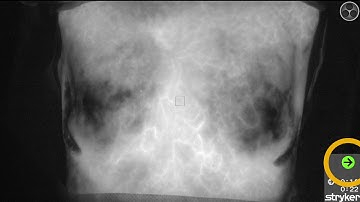

SPY-PHI to Visualize Perfusion After Above-the-Knee Amputation